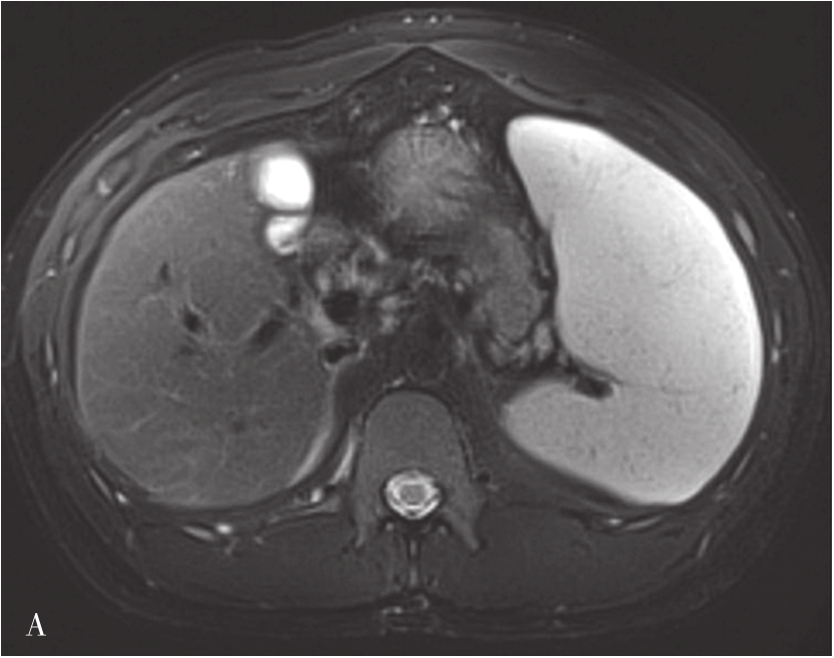

肝硬化的MRI表现(图5-21-41)在形态学改变方面与CT相似。肝硬化再生结节T 1 WI一般表现为稍高或等信号,T 2 WI表现为稍低信号或等信号,该信号改变与再生结节中含铁血黄素沉积有关,再生结节T 2 WI表现低信号,且DWI呈等或稍低信号较为特征,借此可与结节性肝癌或血管瘤鉴别。如发现低信号灶内出现高信号或原有的T 2 WI低信号再生结节灶转变为高信号,或DWI上信号增高,多提示结节癌变。门静脉高压表现为门脉主干扩张,其表现类似CT表现。侧支循环由于其内的流空效应,表现为明显扭曲扩张的血管或结节呈低信号灶。梯度回波序列则表现为高信号。无需使用造影剂即可识别,较CT平扫更具特征性。目前可通过静脉注射GD-DTPA后行门静脉MRI检查,可较清楚地显示扩张的门静脉,并能显示脾静脉及其门-体静脉周围侧支循环。

图5-21-41 肝硬化的MRI表现

A.肝硬化脂肪抑制T 2 加权像;B.T 1 加权像;C、D.增强扫描动脉期及门脉期图像:肝脏体积缩小,肝裂增宽,脾明显增大,T 1 WI图像可见多发略高信号肝硬化再生结节,门脉期示门静脉主干增宽